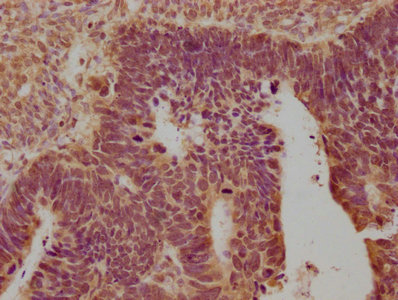

IHC (Immunohistochemistry)

(IHC image of AAA243510 diluted at 1:100 and staining in paraffin-embedded human ovarian cancer performed on a Leica BondTM system. After dewaxing and hydration, antigen retrieval was mediated by high pressure in a citrate buffer (pH 6.0). Section was blocked with 10% normal goat serum 30min at RT. Then primary antibody (1% BSA) was incubated at 4 degree C overnight. The primary is detected by a biotinylated secondary antibody and visualized using an HRP conjugated SP system.)